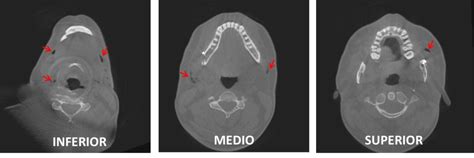

Inmediatamente la paciente fue traslada al servicio de urgencia del Hospital Dr. Hernán Henríquez Aravena, siendo reexaminada allí, y realizándose los exámenes de rigor. Se le tomaron radiografías de cabeza y cuello, las cuales confirmaron la presencia de aire en los tejidos subcutáneos. El diagnóstico de enfisema subcutáneo fue hecho a partir de los hallazgos y la vía de entrada se asumió el surco gingival. Se le indicó continuar el régimen de antibióticos con ciprofloxacino que ya estaba tomando y además una terapia analgésica en base a Naproxeno de 550 mg un comprimido cada doce horas por tres días.

En la mayoría de los casos este signo es detectado inmediatamente, sin embargo, existen informes de que puede presentarse con posterioridad dificultando su diagnóstico. El dolor, aunque no se presentó en este caso, puede acompañar al enfisema subcutáneo producto de la tensión a que pueden ser sometidos los tejidos afectados. Las radiografías de las zonas comprometidas confirman el diagnóstico al revelar la presencia de aire en los tejidos blandos.